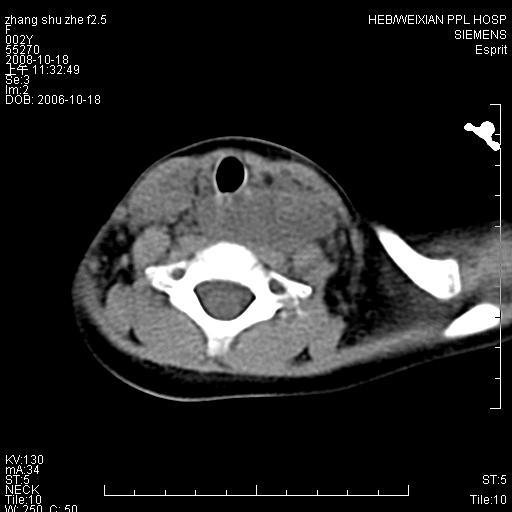

以下是引用dyqct在2009-2-10 21:04:00的发言:[br]年龄?性别?有发烧吗?[br]鼻咽部、口咽部、喉咽部及颈椎前间隙广泛肿厚,明显占位效应并致相应组织变形。ct值22-28hu。[br]考虑:1、颈前脓肿可能性大;[br] 2、建议增强或治疗后复查。

以下是引用jiangjing在2009-2-11 11:37:00的发言:[br]急性病程,鼻咽部、口咽部、喉咽部及颈椎前间隙广泛肿厚,明显占位效应并致相应组织变形.考虑颈部感染性病变(脓肿?);建议行进一步检查。